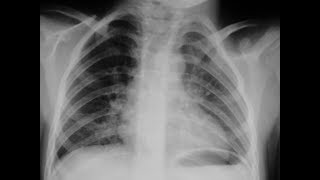

П.В. Гаврилов - Диссеминированный туберкулез легких: скиалогическая картина

Национальная Школа Рентгенорадиологии, 27-28 апреля, г. Владивосток.

Национальная школа рентгенорадиологии Дифференциальная диагностика диссеминированного туберкулеза

Дифференциальная диагностика диссеминированных процессов в легких и туберкулеза

В структуре легочной патологии диссеминированные заболевания составляют около 20%. На сегодняшний день насчитывается более 200 ...